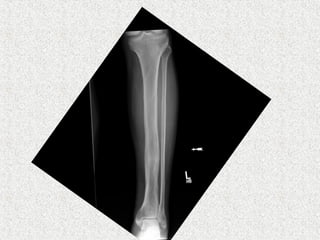

 X rays

 Transverse lucencies/pseudofractures

On the convex surface of weight bearing bone

 Focal bone resorption

 Disorded trabecular pattern

 Expanded bone

 Cortex thick

 Flame shaped/blade of grass osteolytic wedge

 sclerosis

 A banana fracture

 Complete

 horizontally oriented pathological fracture

 seen in deformed bones affected

  incremental fractures

 A type of insufficiency fracture.